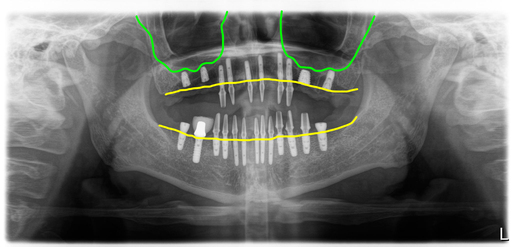

상악은 양쪽 모두 상악동 리프팅 방식의 간단한 뼈이식을 하면서 총 10개의 임플란트를 식립했으나, 뼈이식한 부위의 4개는 초기고정이 좋지 않아서 잇몸 속에 두고 앞쪽에 심은 6개의 임플란트를 이용해서 8개의 임시치아를 만들었어요.

그리고 하악은 이전에 심은 임플란트는 그대로 두고 추가로 12개의 임플란트를 심어서 10개의 임플란트에 지대주 연결해서 임시치아를 적용했습니다.

이렇게 해서 수술당일 임시치아를 해 드렸어요.

6개월후 스캔바디 스캔

수술 후 6개월째 스캔바디를 넣고 스캔을 했습니다. 이렇게 하면 잇몸 속에 심겨진 임플란트의 위치를 알 수 있어 지대주와 크라운을 디자인 할 수 있게 됩니다.

상악 어금니 부분에는 잇몸 속에 임플란트가 있어서 절개를 해서 스캔바디를 위치시켰고, 절개를 했기 때문에 2주 후에 최종 세팅을 했습니다.